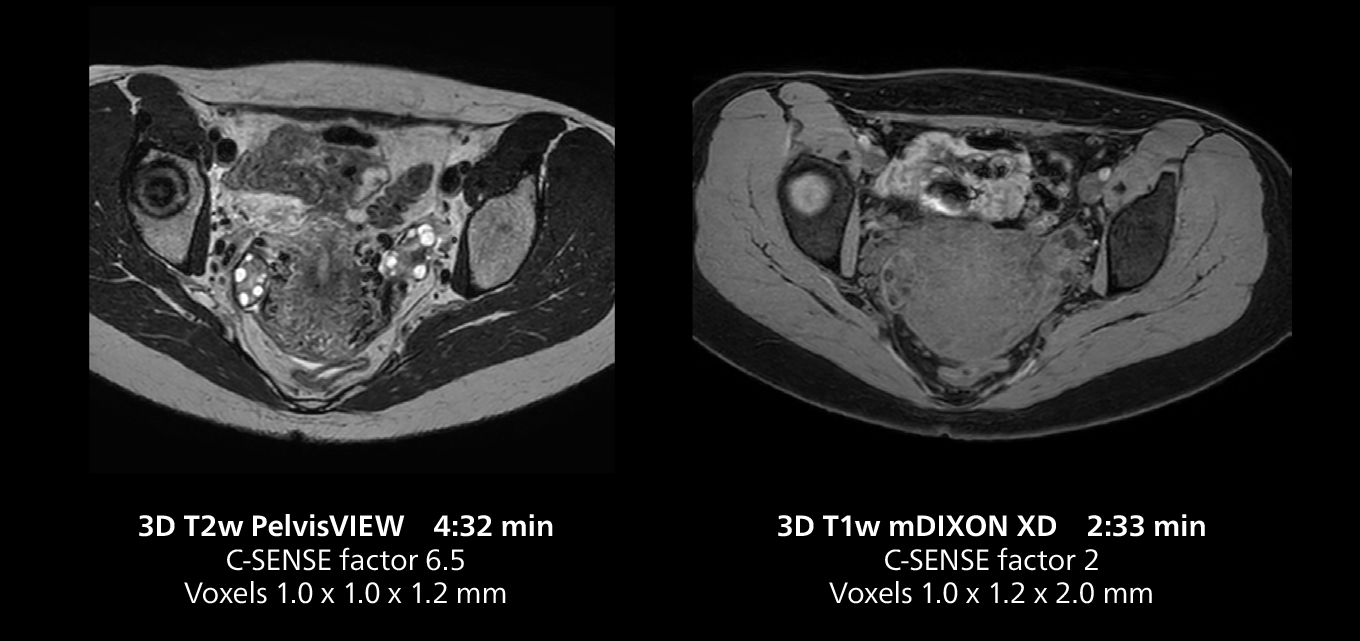

Liver imaging using MR 5300

This case includes 3D free breathing and 4D dynamic free breathing MRI of a metastasized liver. A high quality fatsat sequence with good resolution is obtained in 1:36 minutes with T2-weighted MultiVane XD.

Liver imaging using MR 5300

This case includes 3D free breathing and 4D dynamic free breathing MRI of a metastasized liver. A high quality fatsat sequence with good resolution is obtained in 1:36 minutes with T2-weighted MultiVane XD.

Free-breathing scans provide reproducibility and patient comfort

Dr. Gellée highlights the robust free-breathing scans as “the feature that makes the biggest difference in my daily work. The 3D free breathing sequences are very reproducible, and the axial acquisition is very good. For example, in endometriosis, which is one of my focus areas, it provides high contrast and good resolution so that I can see small details. We also use free breathing for liver and pancreas imaging. In multi-phase liver studies, 4D Free Breathing delivers 3-second temporal resolution, making a dynamic scan with more than one arterial phase possible.”

She also uses free breathing with 3D mDIXON to obtain in-phase, water and fat images in a single scan. “It is very reproducible before and after gadolinium, which makes it useful for liver imaging,” she adds.